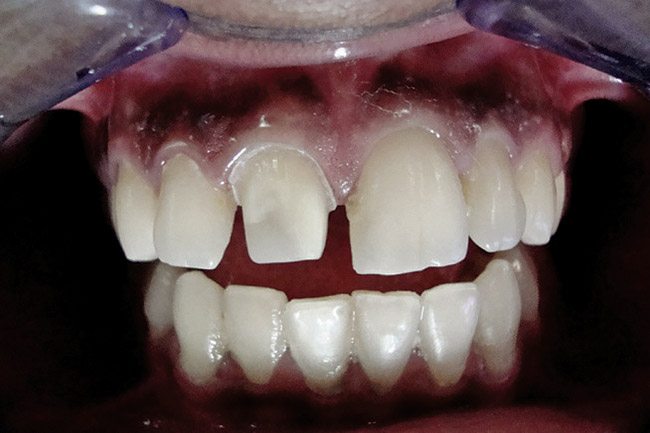

Figure 2  Caries extending cervically on upper right incisors.

Figure 2

Figure 3  Placement of rubber dam with application of cervical clamp on central incisor for extra retraction.

Figure 3

Figure 4  Final composite restorations with respect to upper right incisors.

Figure 4